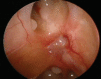

Objectives Bilateral anterior skull base (ASB) defects following endoscopic endonasal tumor resection are most commonly repaired utilizing multilayered reconstruction with a vascularized mucosal flap. Single-layer closure of large ASB defects has been described in the literature but this technique has yet to gain a widespread use. We report our experience with a series of patients who underwent reconstruction of large ASB defects using a single-layer intradural graft, without nasoseptal flaps. We also compared the use of acellular dermal matrix (AlloDerm, LifeCell, Branchburg, New Jersey, United States) or collagen matrix xenograft (Duramatrix, Stryker, Kalamazoo, Michigan, United States) as the graft biomaterial. Design A retrospective case series. Setting Tertiary academic medical center. Main Outcome Measures Postoperative cerebrospinal fluid leak, the number of postoperative debridements, the number of postoperative infections, and time to remucosalization. Results Two patients were reconstructed with AlloDerm and three with Duramatrix, with all patients receiving postoperative external beam radiation. There were no postoperative cerebrospinal fluid leaks identified in these patients during follow-up. The AlloDerm group showed increased postsurgical crusting, the number of clinically apparent postoperative infections, and an increased time to remucosalization. Conclusions Single-layer repair without a vascularized mucosal flap is a viable method of skull base repair for large ASB defects. We found repair with Duramatrix was superior, with less graft crusting and infection, requiring fewer debridements.